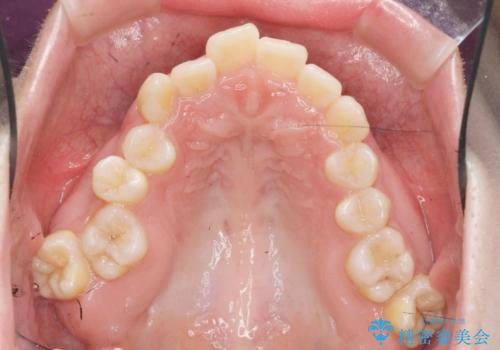

サクソフォン(アルト)の演奏で崩れてしまった歯並び、マウスピース矯正治療

- 高校時代の吹奏楽の部活でサクソフォン(アルト)を担当、「一生懸命練習をしすぎて気づいたら歯並びが悪くなっていた。矯正治療を受けたい!。」

とマウスピース矯正を希望され来院されました。

口腔内の清掃状態の良さに加えて、マウスピースを毎日きっちりと装着し、しっかりと使用していただけたことからワイヤー矯正は行わずにきれいに歯並びを治すことができました。

途中顎位が変わり、マイクロインプラントを併用した上顎臼歯の遠心移動が必要となったため治療が長期化しました。